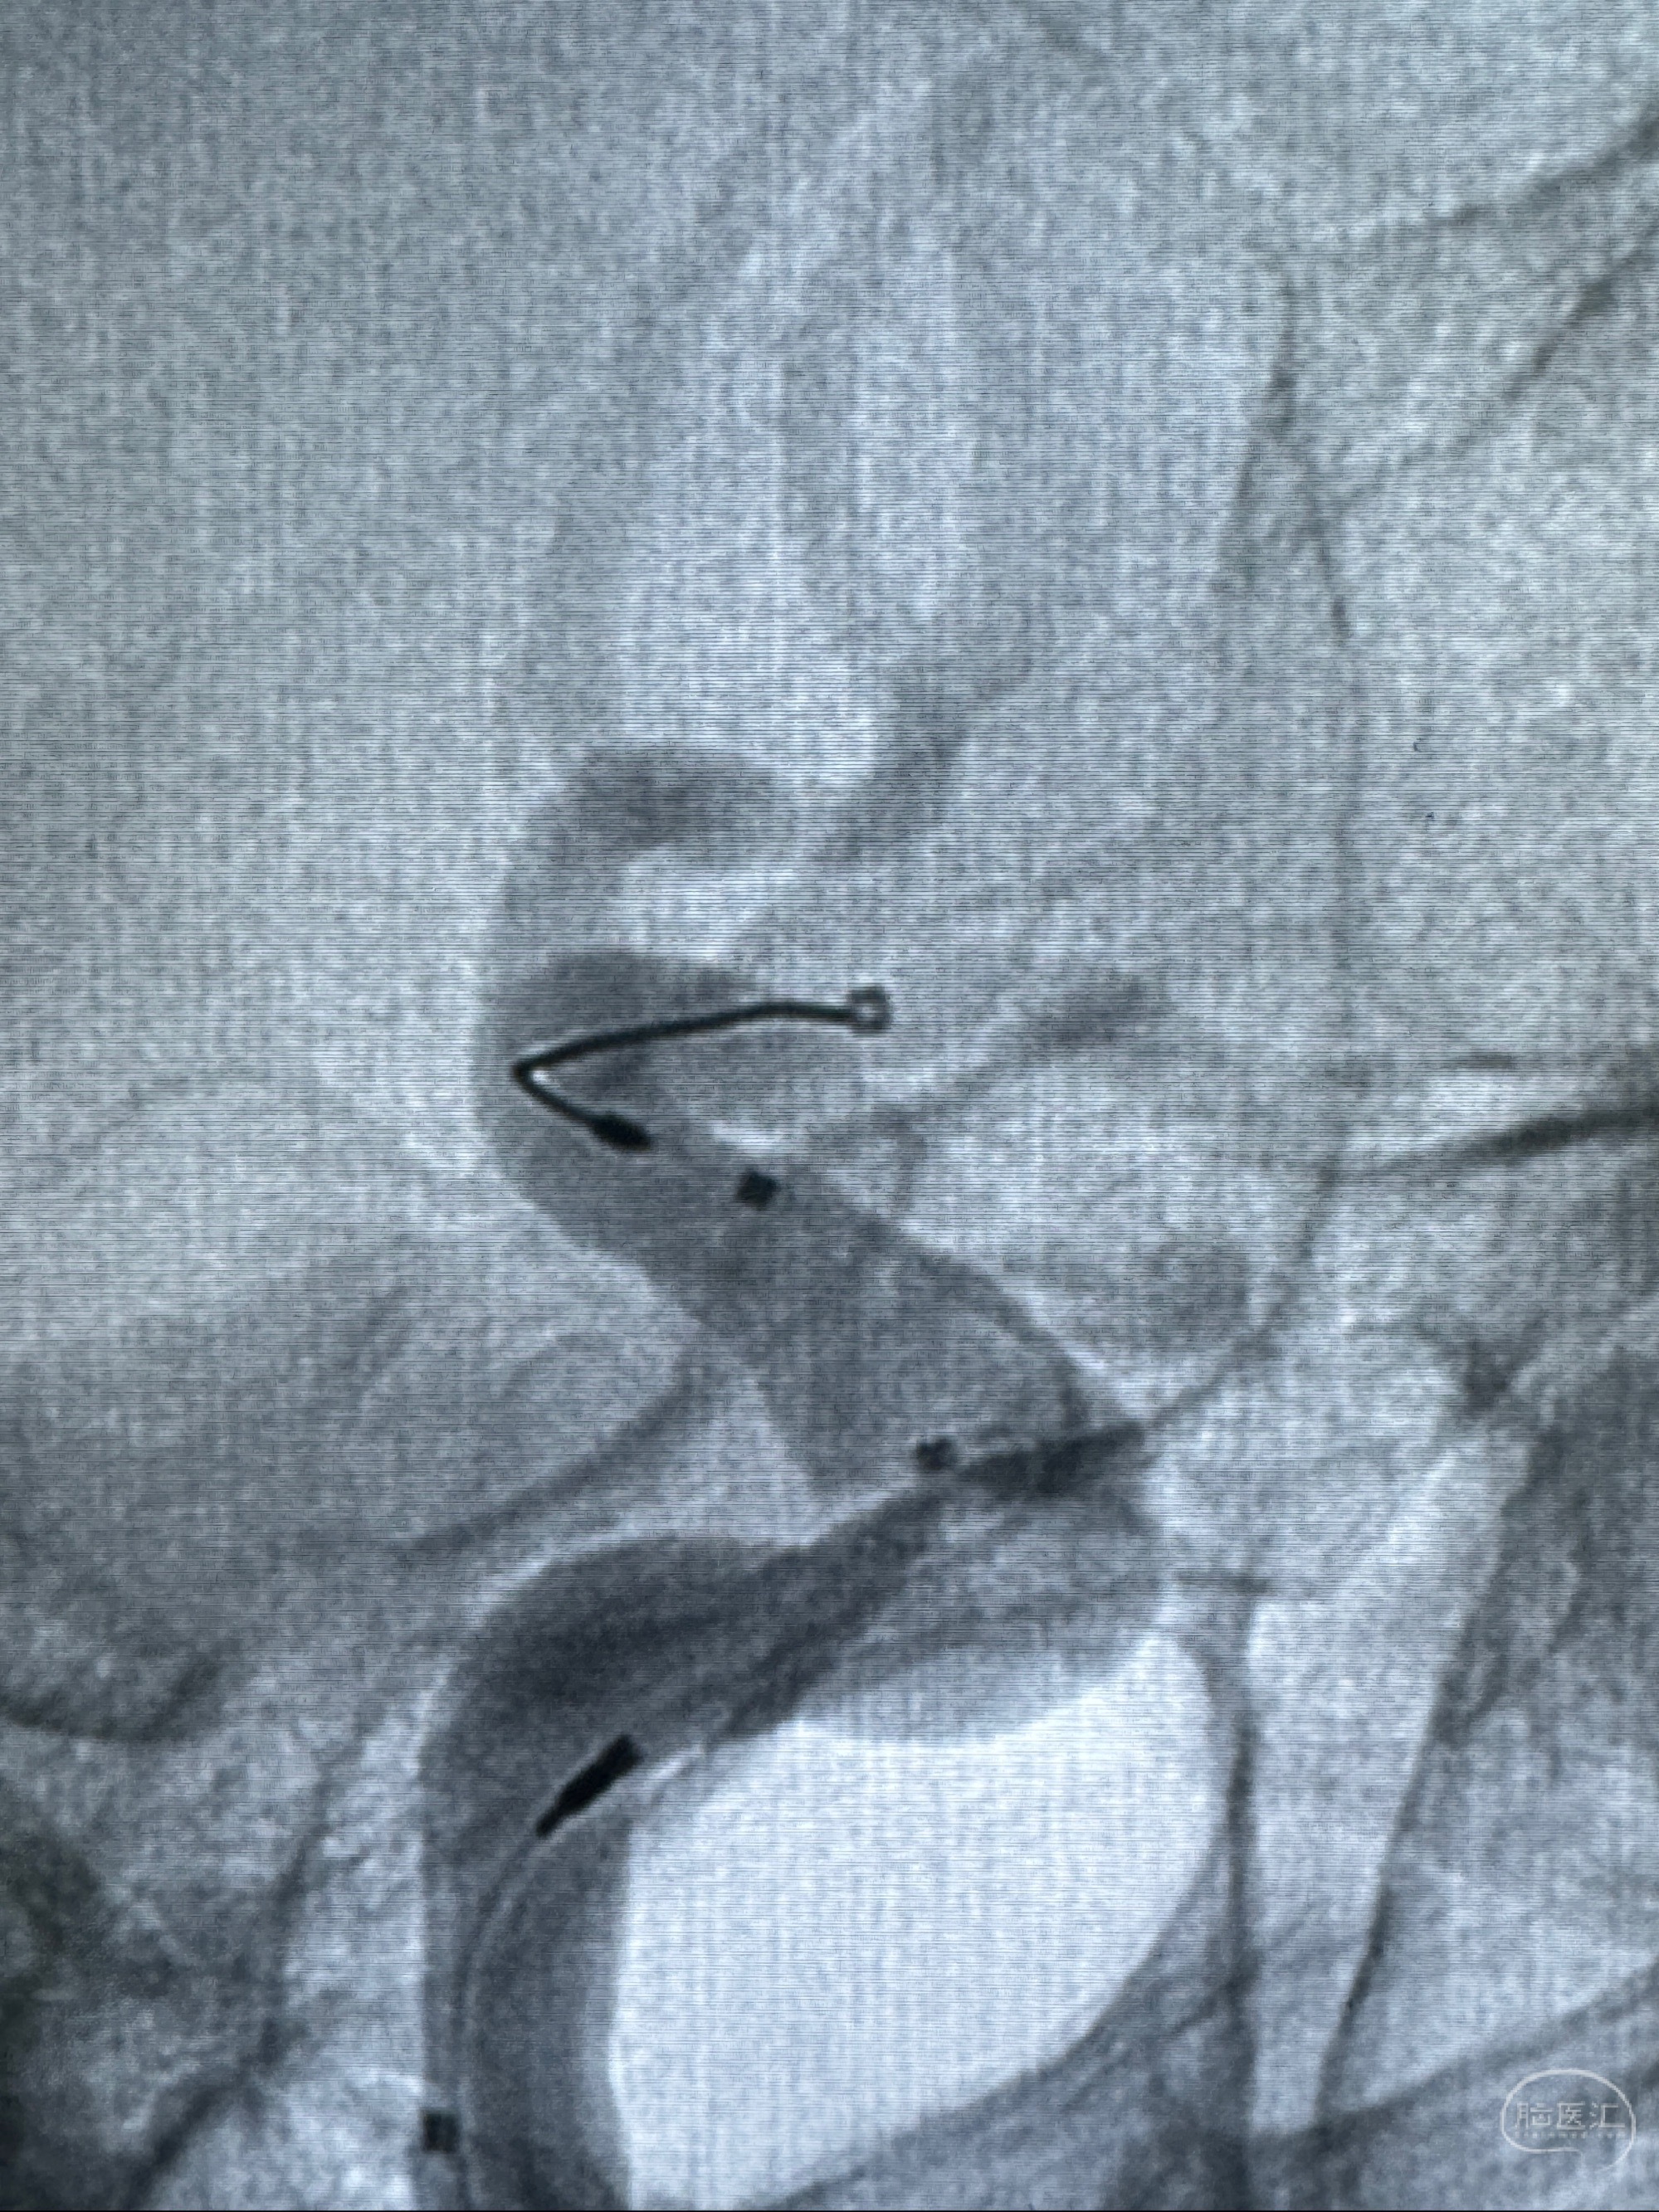

2023-11-13DSA:左侧颈内动脉眼动脉后壁动脉瘤

2023-11-29全麻下行NeuroformEZ4.5-20mm支架辅助栓塞